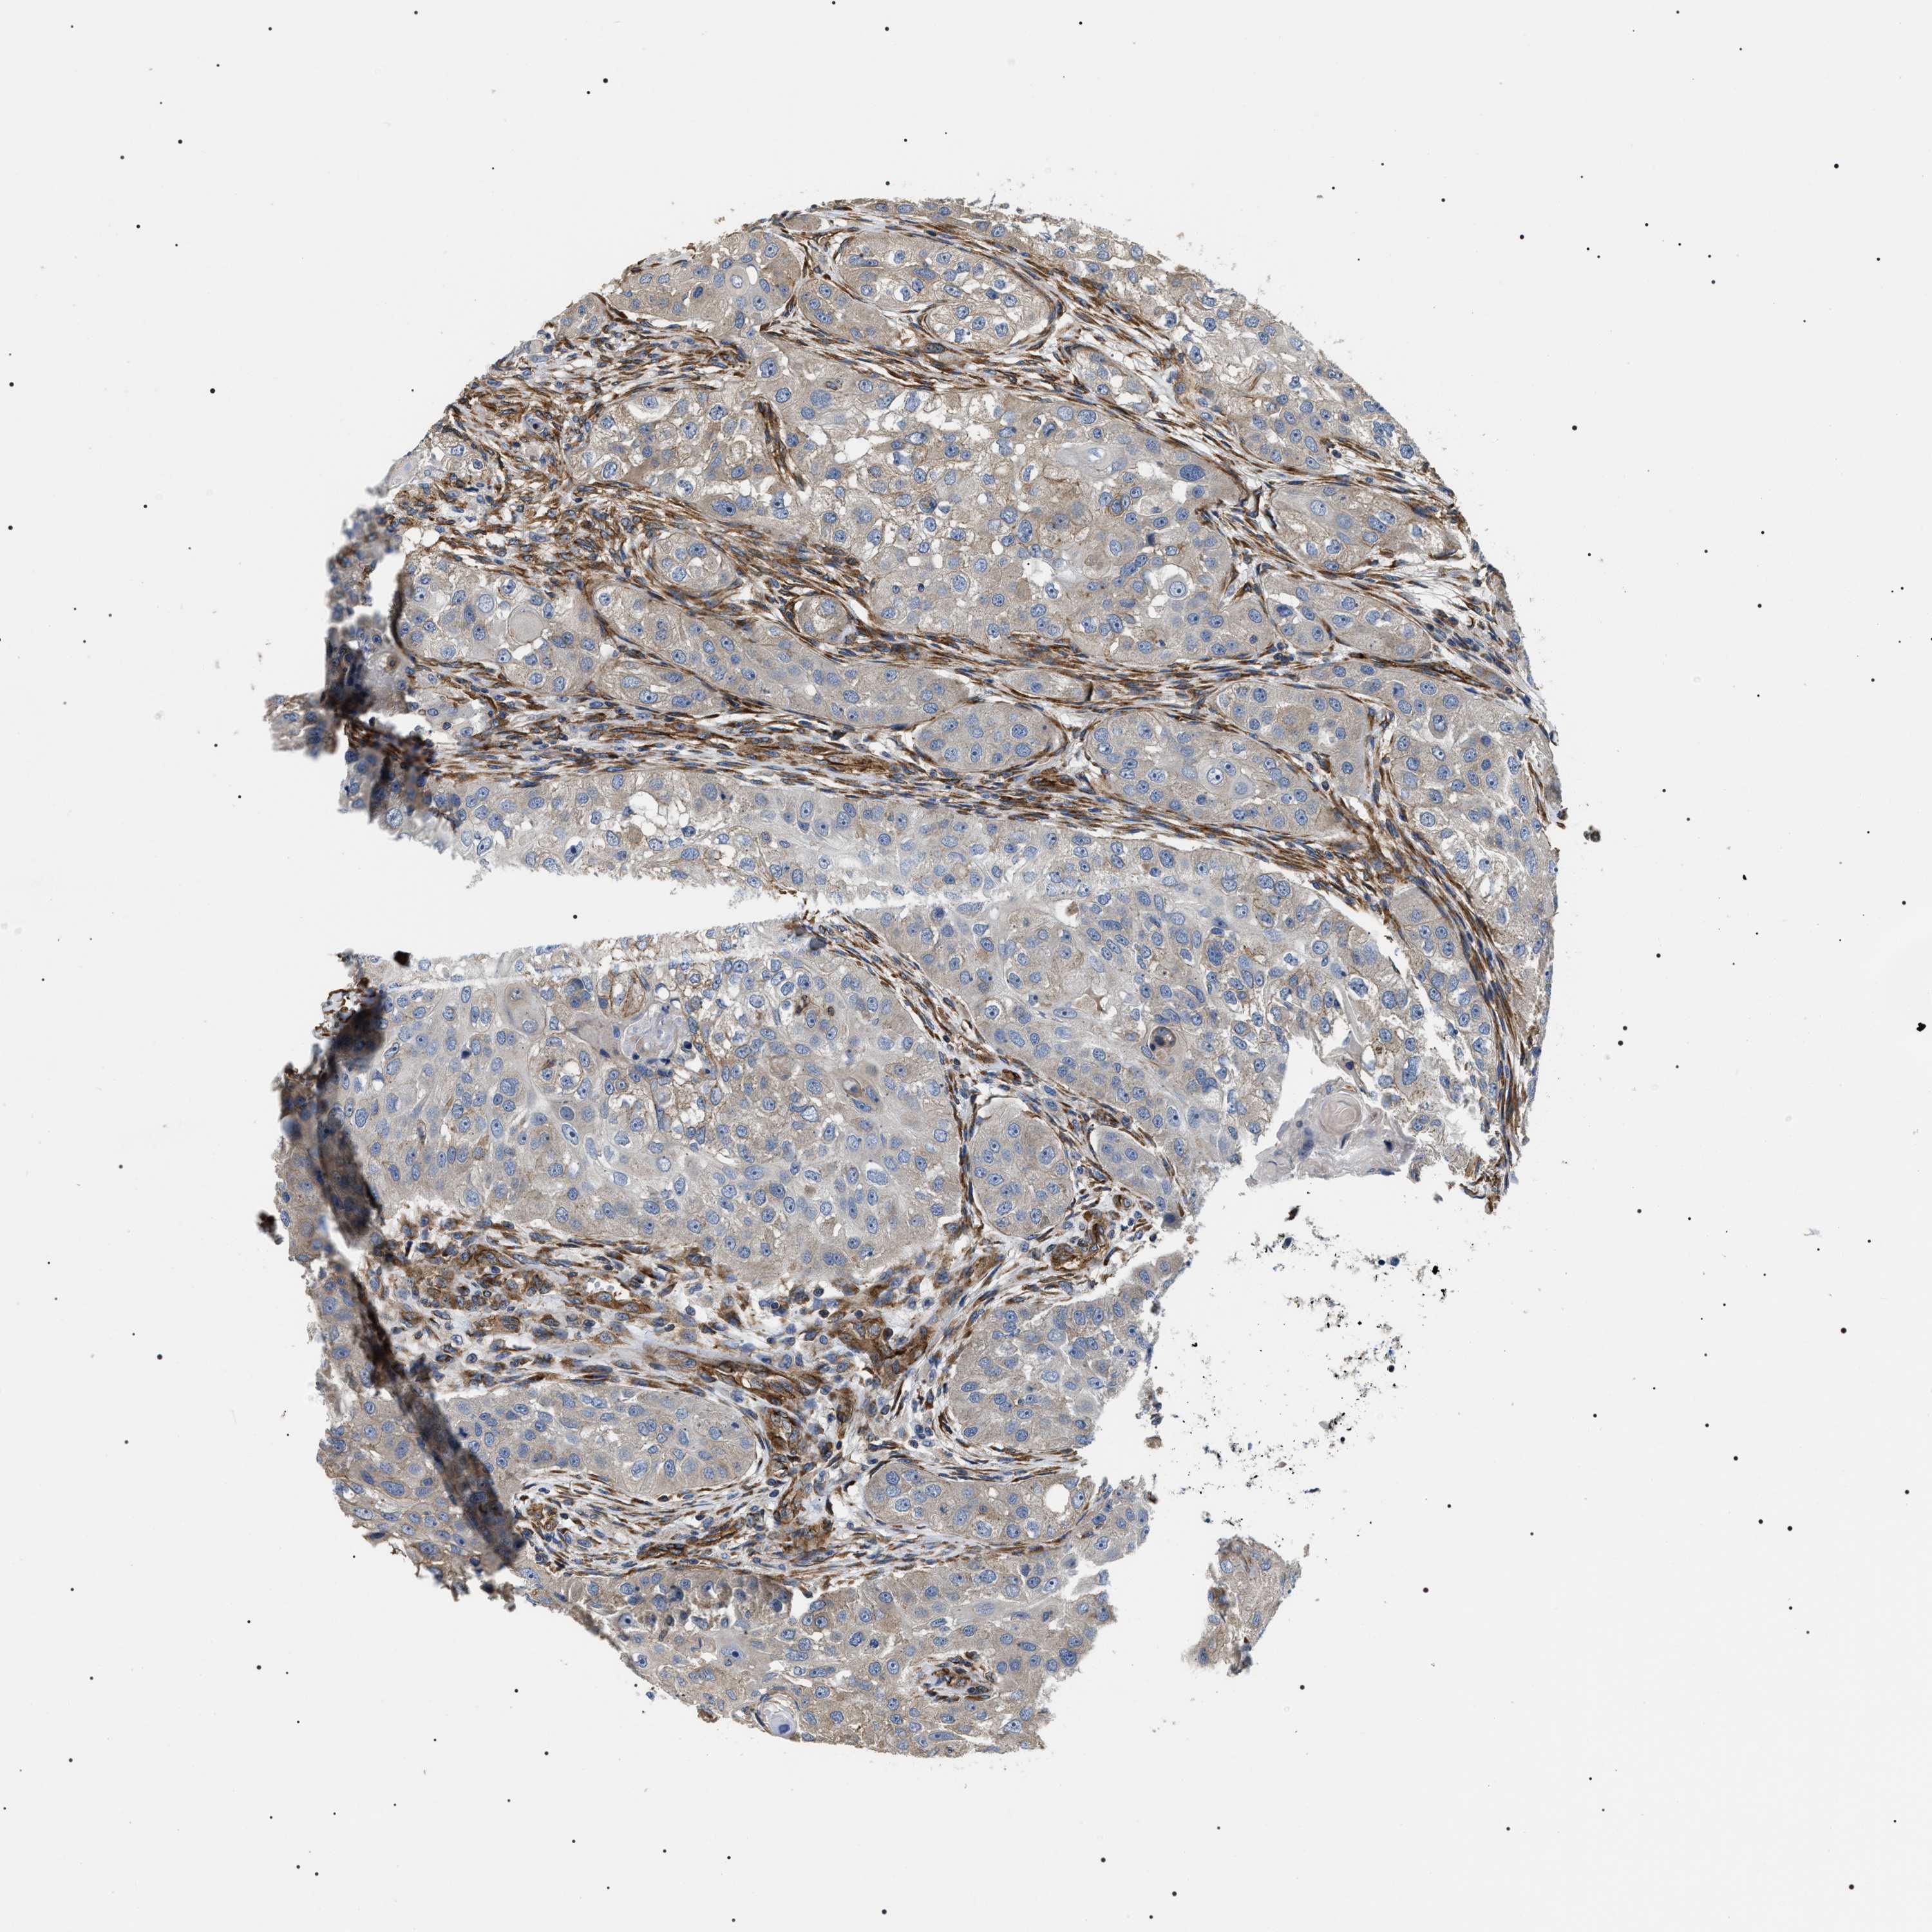

HEAD AND NECK CANCER - Protein expressioni

A mouse-over function shows sample information and annotation data. Click on an image to view it in a full screen mode. Samples can be filtered based on level of antibody staining by selecting one or several of the following categories: high, medium, low and not detected. The assay and annotation is described here.

Antibody stainingi

Antibody staining in the annotated cell types in the current human tissue is reported as not detected, low, medium, or high, based on conventional immunohistochemistry profiling in selected tissues. This score is based on the combination of the staining intensity and fraction of stained cells.

Each image is clickable and will lead to virtual microscopy that enables deeper exploration of all samples and also displays staining intensity scores, fraction scores and subcellular localization as well as patient and tissue information for each sample.

Antibody HPA020386

Staining

High

Medium

Low

Not detected

Intensity

Strong

Moderate

Weak

Negative

Quantity

>75%

75%-25%

<25%

None

Location

Nuclear

Cytoplasmic/membranous

Cytoplasmic/membranous,nuclear

Squamous cell carcinoma, NOS

Squamous cell carcinoma, metastatic, NOS

Adenocarcinoma, NOS